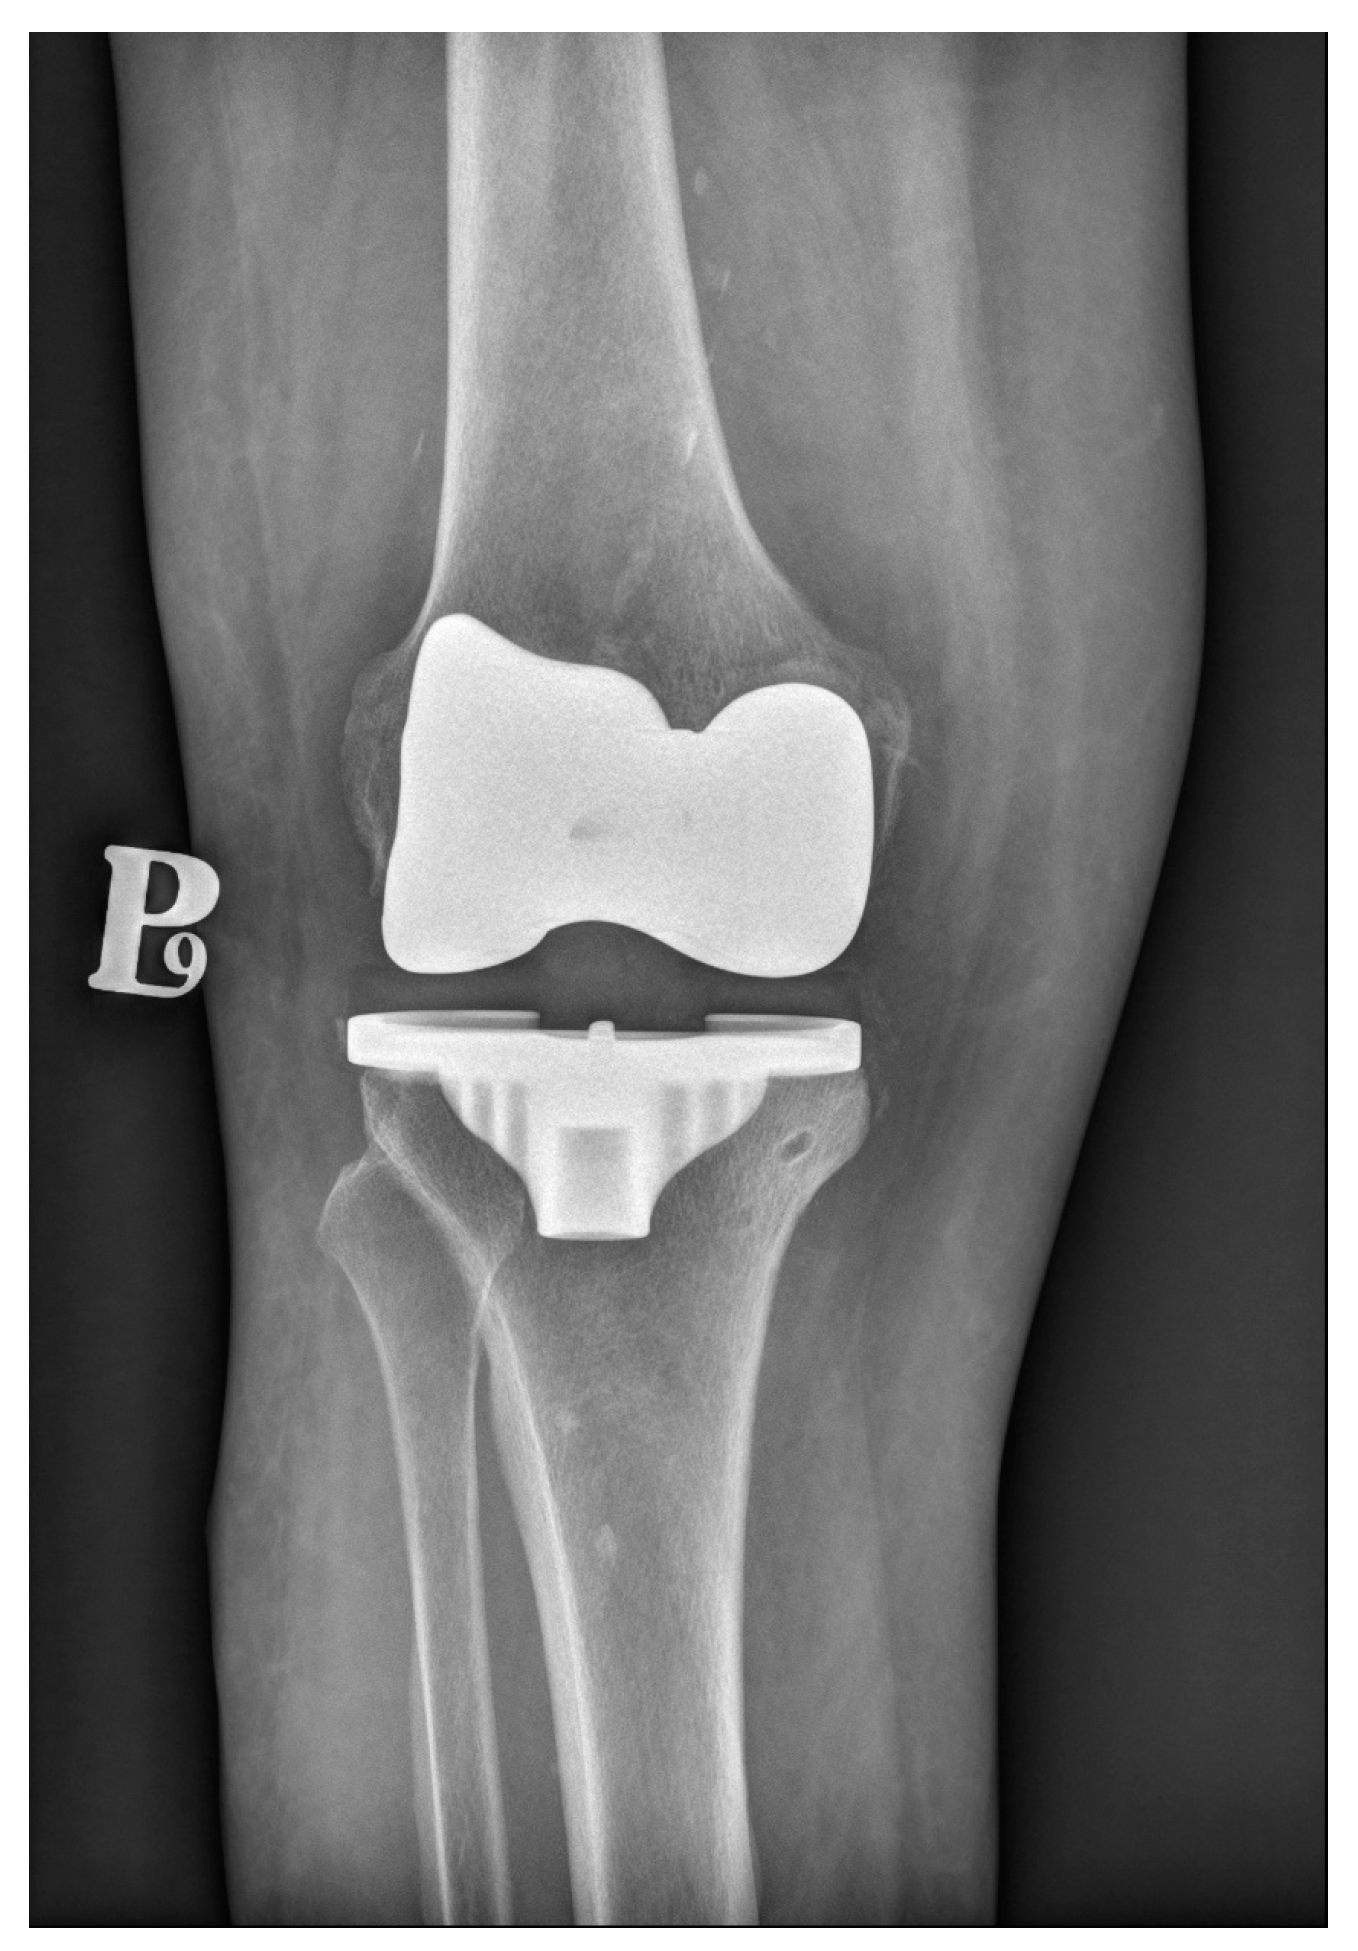

3. Cemented Knee Replacement

4. Cementless Knee Replacement